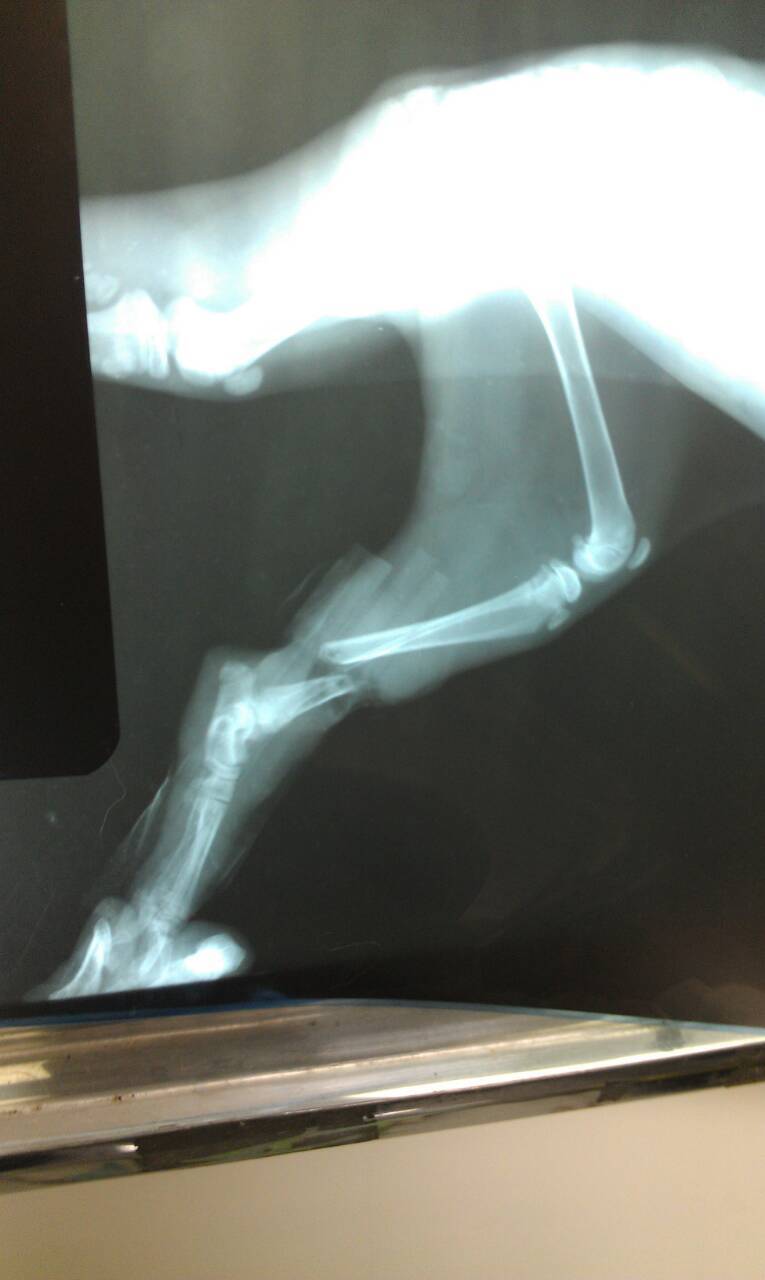

主題: 補獸夾小小貓 申請者姓名: 詹小君 花色: 申請日期: 2014-03-02 01:19:16 申請者部落格: 申請者臉書網址: 所在縣市/合作醫院: 台中市/聖欣動物醫院 治療費用: 19000元 需求人數: 21人 已結案 (2014-03-24 18:12:11) 報名人員: 裘爸(已付款)、Teresa Kao(已付款)、CAsperR(已付款)、點子(已付款)、Rocky Chen x3(已付款)、米雪路(已付款)、Ann Cat(已付款)、Milkbau Lu、liumon(已付款)、Vanessa Cheng(已付款)、momo(已付款)、Britney(已付款)、謝佩芳(已付款)、老皮(已付款)、阿呆的貓(已付款)、Wesley Kao(已付款)、C-shan Cheng(已付款)、Hide(已付款)、FiFi、Lynn Wu(已付款)、小四(已付款)、 候補人員: 陸媽咪、 動物病情說明: 除夕這天,在忙碌的準備年夜飯時,

忽然聽見媽媽的驚呼聲,說我家旁邊的果園裡居然有一隻拖著捕獸夾的小小貓,

和媽媽手忙腳亂的抓到小小貓後,趕緊幫他鬆開捕獸夾,小小貓的腳哪經得起捕獸夾,骨頭已經明顯的被捕獸夾夾斷了,一直晃來晃去,由於正值吃年夜飯的時間,醫院早已休息,只好先用筷子幫牠把腳先固定起來,因為不知道什麼時候才能聯繫得上醫院。

晚上9點,聯絡上聖欣的醫生,立即將小小貓帶去醫院治療,醫生說小小貓被捕獸夾夾傷約有三四天了,傷口可直接見骨,周邊傷口潰爛嚴重,

拍了X光片,確定骨折,所以先裝了骨釘固定骨頭。